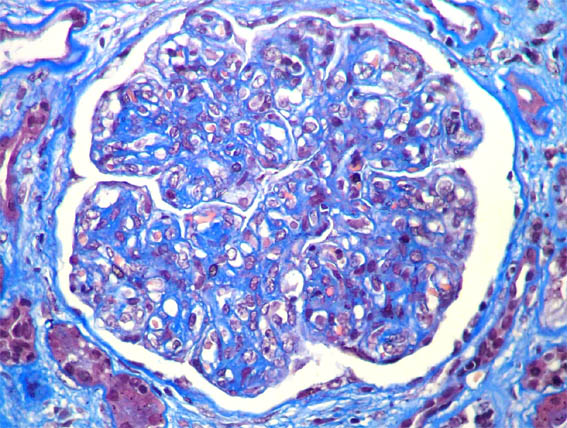

Figure 3.

Masson's

trichrome stain,

X400.